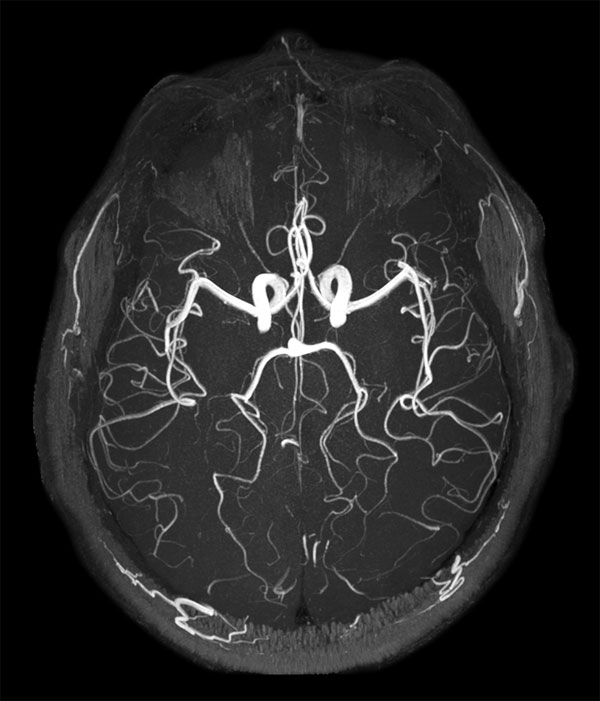

dS SENSE in Brain Imaging

Used Solution

• Clinical Application